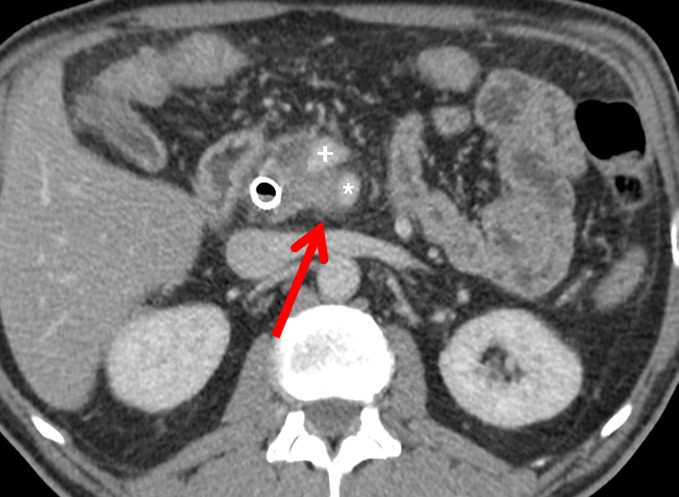

Il a pour but l’exérèse complète d’une tumeur localisée, avec des marges supérieures à 1 mm (résection R0). La survie médiane est alors de 30-40 mois. La plus importante au plan pronostique est la marge rétrovasculaire, ou lame rétroporte (tissu graisseux, lymphatique et nerveux, située en arrière de la VMS et la VP et au contact de l’AMS ; fig. 1A).

Évaluer la résécabilité secondaire d’une tumeur borderline après CT  RCT peut être difficile et repose sur un faisceau d’arguments cliniques (disparition des douleurs cœliaques, reprise de poids), biologiques (baisse du CA 19-9 sérique) et radiologiques (réduction même partielle du contact tumeur-axe vasculaire, diminution même modérée du diamètre tumoral ; fig. 1B). Après traitement d’induction, on propose une exérèse s’il n’y a pas de progression en TDM et si le taux de CA 19-9 sérique reste bas ou diminue nettement (< 50 %).